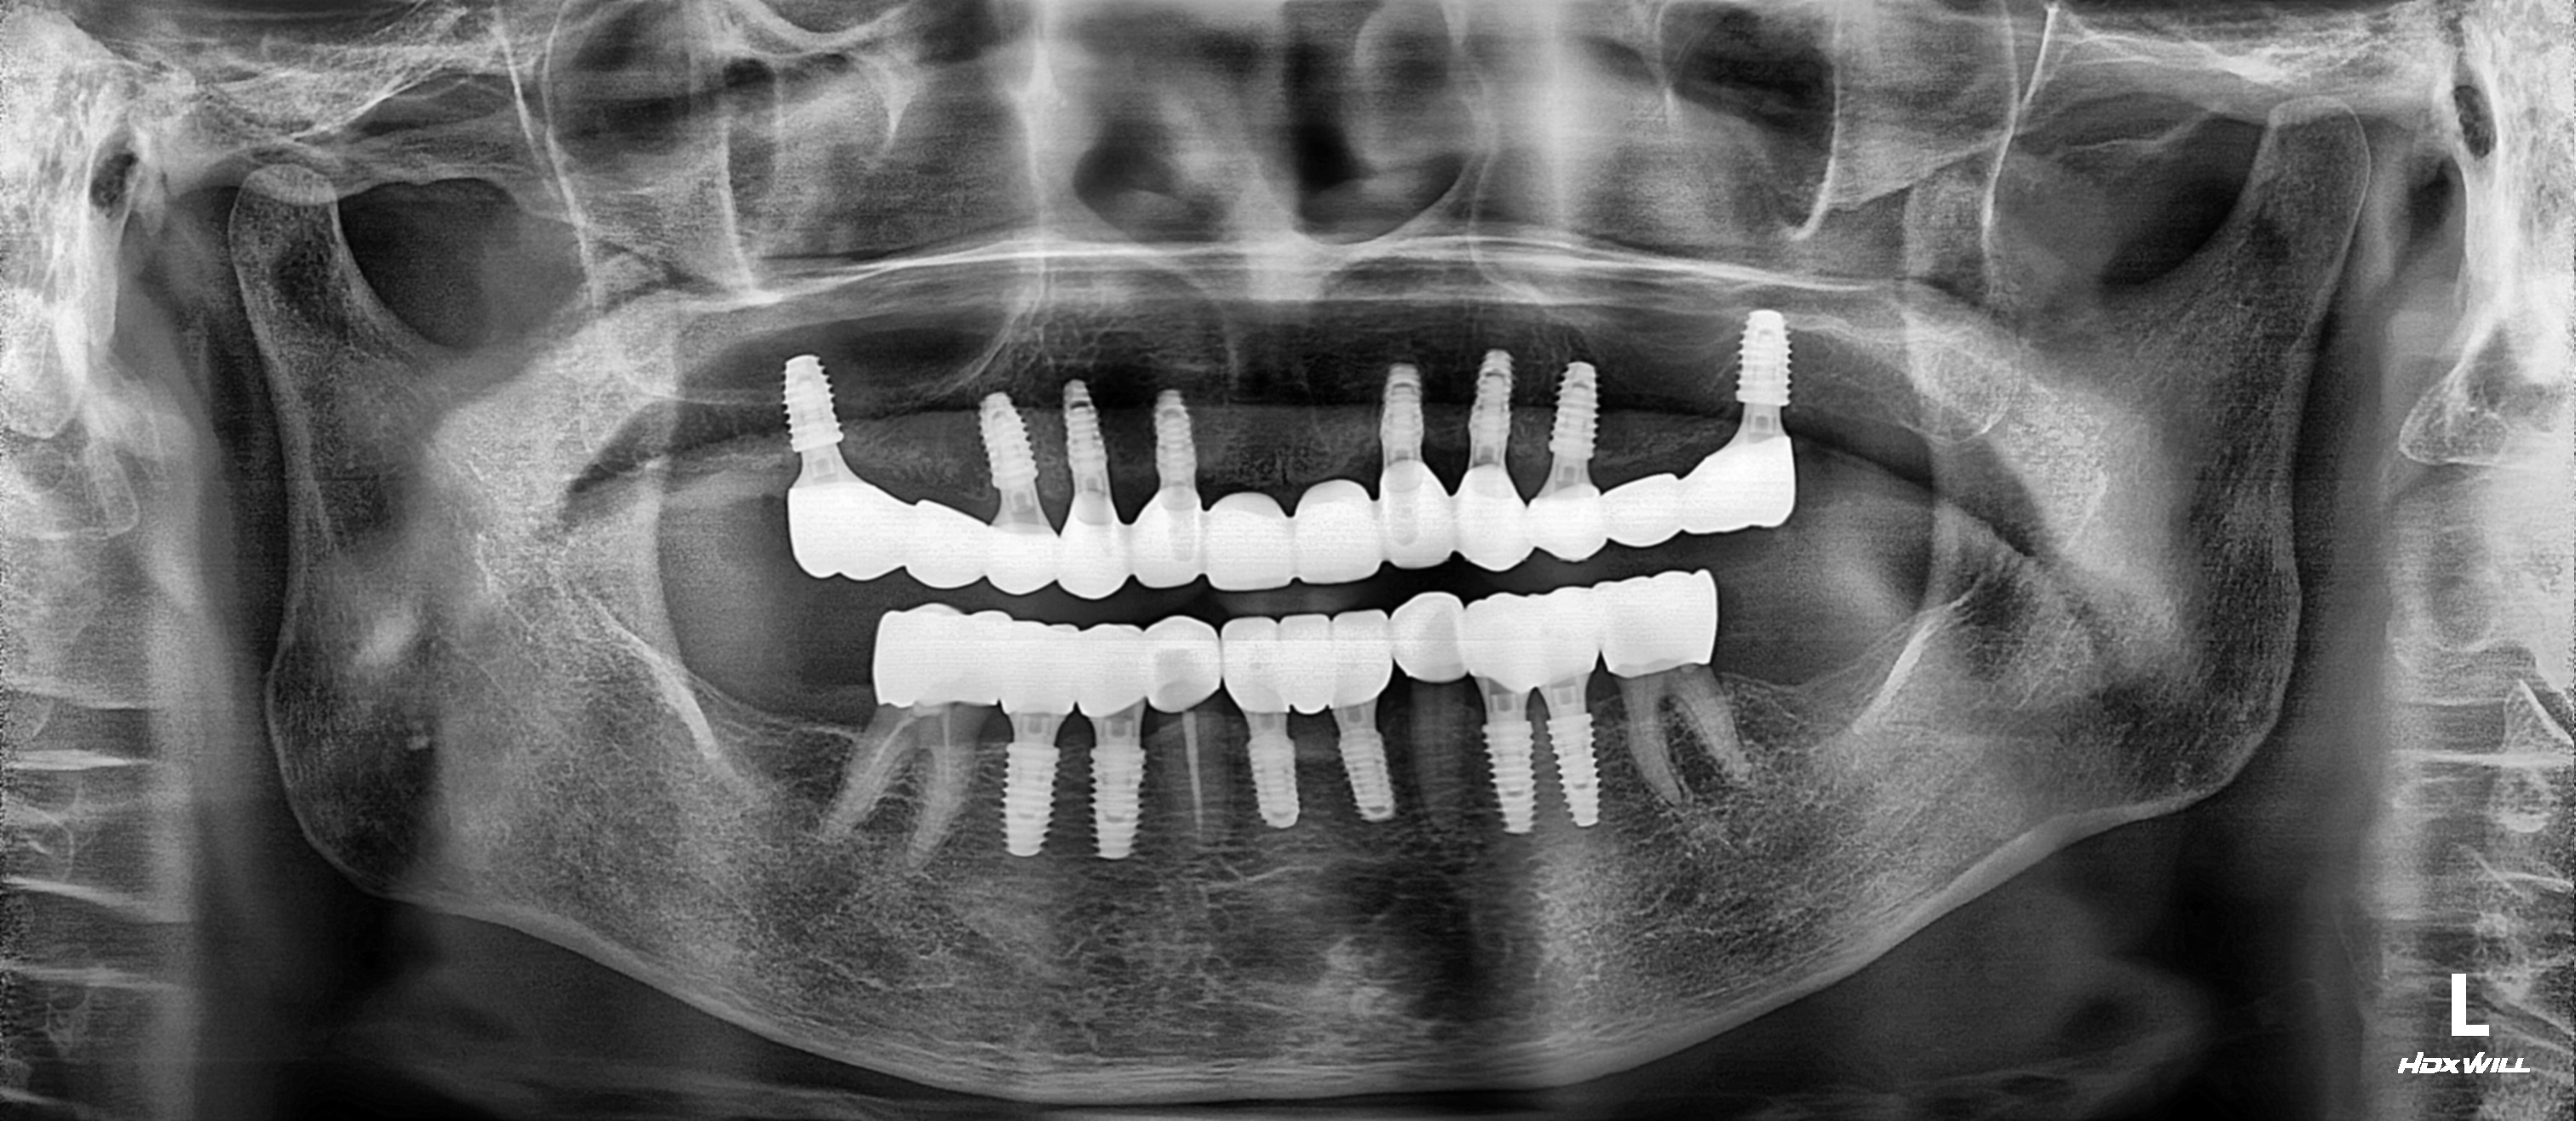

치료 후 파노라마

상악은 윗니 상태가 매우 좋지 않아 전악 8개를 식립하였습니다.

하악은 살릴 수 있는 치아는 충치를 치료하여 크라운 수복하고, 임플란트를 이용해 교합과 저작을 완성하였습니다.